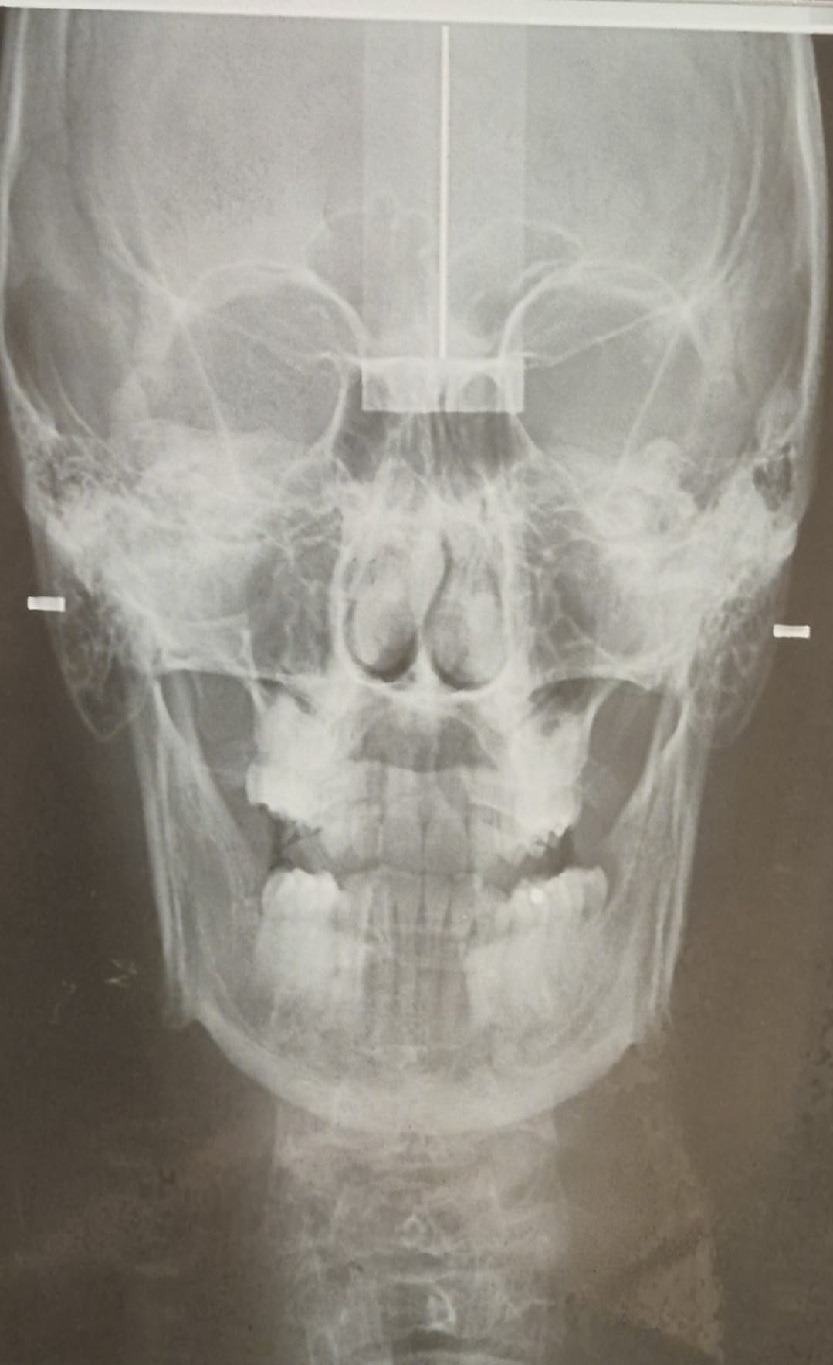

Esistono anche lastre rx per farvi capire che non siete dei disegnini ma è realtà.

Per ragioni di praticità dobbiamo utilizzare un rapporto scheletrico molto evidente come questo:

Abbiamo coperto volutamente e provocatoriamente i denti perchè lo scheletro si vede ugualmente non simmetrico anche senza bocca e denti. Si vede anche senza una lastra:

A livello di rx possiamo dire che cranio e mandibola, prima e dopo, sono diventati simmetrici applicando la scoperta del Meccanismo OG.

I condili della mandibola si riallineano, si riallineano le ossa SUI TRE PIANI SPAZIALI ruotando tra loro e inclinandosi fino ad arrivare ad una posizione di simmetria e di EQUILIBRIO MECCANICO ABITUALE.

Per la rx a destra abbiamo ricevuto complimenti anche da una prestigiosa università italiana che è tra le più prestigiose del mondo.

Un esempio di denti bellissimi senza malocclusione ma su un rapporto scheletrico in Dis-Equilibrio:

Un esempio di rapporto scheletrico in Equilibrio con malocclusione:

Secondo voi quale dei due individui delle rx ha una condizione di vita migliore (in condizioni sane ma anche meno sane)?

Quello con la malocclusione.

E’ in Equilibrio Meccanico Abituale.